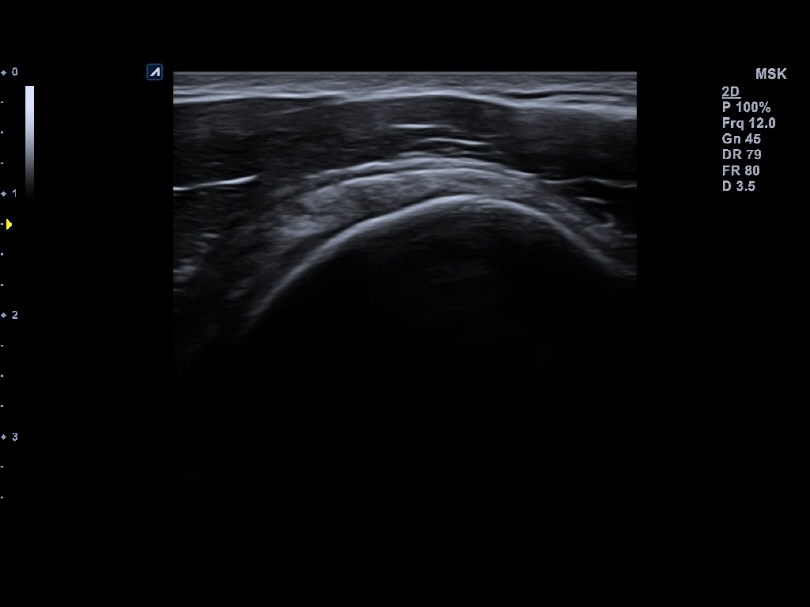

L8-17H

High density linear transducer(8-17MHz)

Application:

Breast, EM, MSK, Vascular, Small Parts